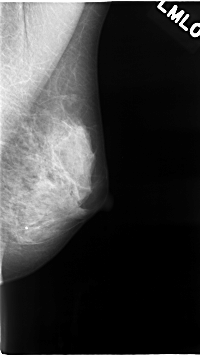

C_0036_1.LEFT_MLO

LEFT_MLO LINES 4640 PIXELS_PER_LINE 2592 BITS_PER_PIXEL 12 RESOLUTION 50 NON_OVERLAY